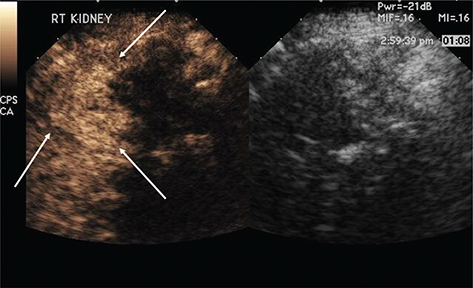

Figure 1 demonstrates the steps in performing a CEUS RFA. Figure 1A is the unenhanced B-mode US before the procedure. In this case, the mass is easily identified. If the mass is not visualized well, a CEUS can be performed to confirm the size and location of the mass. Figure 1B shows the position of the RFA needle in the mass. Figure 1C is the image after the injection of the ultrasound contrast confirming the position of the needle in the mass. Figure 1D shows that there is no flow remaining in the renal mass, confirming complete ablation of the lesion.

Figure 1. Images demonstrating RFA of an RCC. (A) B-mode image of the RCC (calipers) pre-procedure, (B) B-mode image demonstrating positioning of the RFA needle (arrow) in the RCC, (C) image after injection of ultrasound contrast confirming the needle (arrow on low MI B-mode image on right) within the tumor, and (D) CEUS post-procedure demonstrating complete ablation of the RCC (arrow, right).

Figure 2 demonstrates that after the first ablation, a second dose of ultrasound contrast can be performed to evaluate for residual tumor. The CEUS contrast lasts for about 5 min. During the RFA, gas bubbles are generated and appear as CEUS contrast when imaging. Waiting for about 5 min after the completion of the ablation will eliminate this problem. If bubbles still remain in real-time CEUS imaging, the bubbles generated from the procedure will not move whereas the UCA bubbles in residual tumor will be visualized as moving. In this case, a large area of residual tumor (arrows) remains. The CEUS image can be used to reposition the RFA needle into the residual tumor.

Figure 2. Multiple doses of ultrasound contrast can be administered during the RFA procedure. The contrast agents last for about 5 min so that residual enhancement is not present on additional doses. In this case, a CEUS study was performed after the first ablation. Note that there is residual tumor (arrows). The RFA needle can then be repositioned into the residual tumor for additional ablation. This confirms that the tumor is completely ablated at the first setting. The similar process cannot be performed in CT because only one dose of CT contrast can be administered.